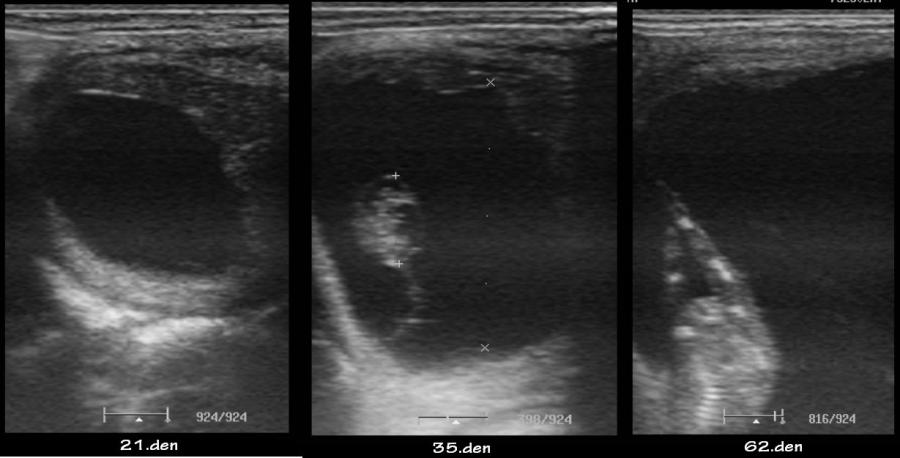

ultrasonografické vyšetření klisny

embryo kolem 21.dne

Embryo 31. den